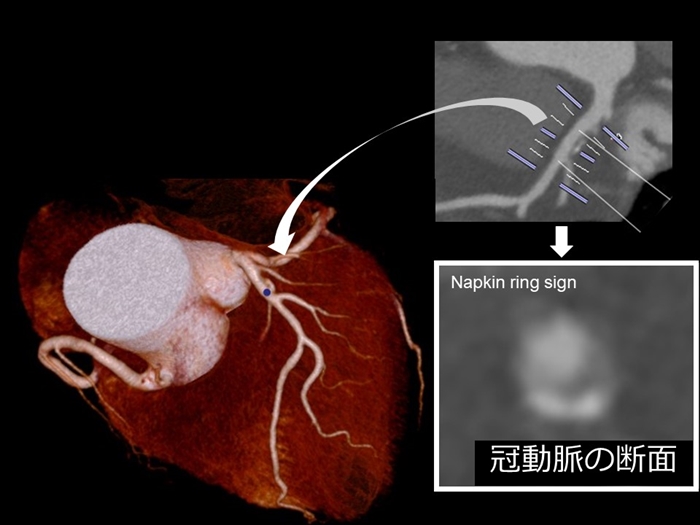

冠動脈CT画像による診断において重要な

脆弱性プラークの代表的な所見は、

以下の通りです。

陽性リモデリング

低CT値プラーク

napkin ring sign

これらの特徴を多くもつ病変ほど、

ACSの発症が多いことが報告されています。

Otsuka K, Fukuda S, Tanaka A, et al. Napkin-ring

sign on coronary CT angiography for the prediction

of acute coronary syndrome. JACC Cardiovasc

Imaging 2013; 6:448?457